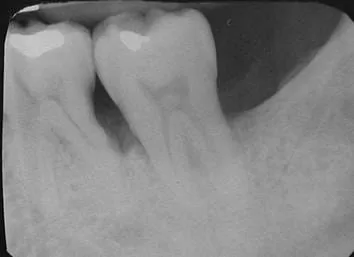

治療前

臨床上患者常有牙齦腫痛化膿的症狀,經放射線檢查發現第二大臼齒遠心端有角狀骨缺損,原因是因為長期清潔不當,導致食物殘渣堆積進而引發牙周病的破壞,故以自體移植骨配合再生膜進行牙周再生手術。

( 圖1: 治療前)